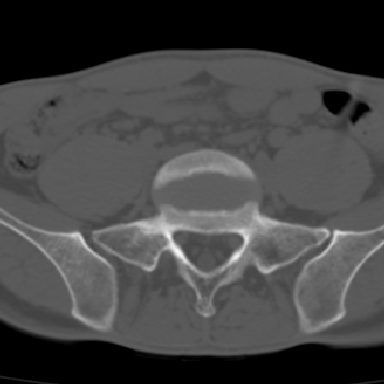

m 30 腰背部不适半年; 清晨时僵硬; 活动症状有所改善

强直性脊柱炎的早期改变!不仅表现为双侧骶髂关节,第5腰椎与骶椎间的关节突关节也有类似改变。

双侧骶髂关节下2/3关节面模糊,毛糙,髂骨侧可见小囊状骨质破坏区,骶髂关节间隙增宽(软骨破坏期)。支持早期强直性脊柱炎。

双侧骶髂关节下2/3关节面模糊、毛糙,可见小囊状骨质破坏区,呈虫咬状改变,周围可见增生硬化.支持强直性脊柱炎早期表现.